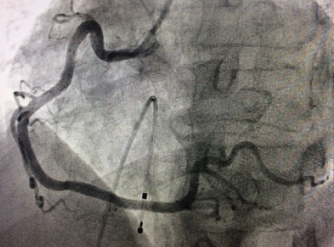

??? 近日,在我院心血管內(nèi)科病房內(nèi),70歲的患者張大爺康復出院,患者及家屬握著醫(yī)生的手連聲道謝。誰能想到,這樣一個思維清晰、開朗健談的老人,10多天前還因為急性ST段抬高型心梗(急性心肌梗塞的一種)瀕臨死亡,在心臟導管室內(nèi)進行爭分奪秒的搶救呢!?突發(fā)胸痛3小時 ??70歲老人病情危急????家住江...